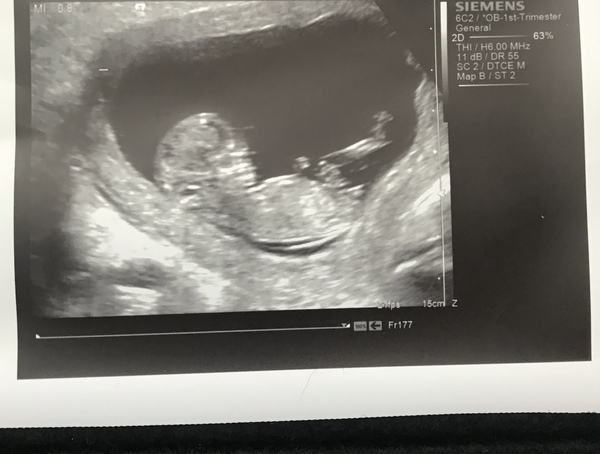

@RichmondLady1981 yes I have a scan pic. This was at 11+4 and I’ll be 15weeks tomorrow. I am at the stage where it doesn’t feel real again, no real symptoms, no real bump growth just plodding along thanks for asking. I hope your well x